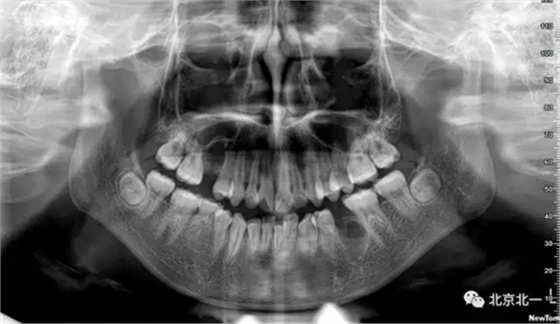

術(shù)后拍片

總結(jié):埋伏牙如果直接硬撬可能會(huì)導(dǎo)致牙槽骨骨折。需要采用微動(dòng)力系統(tǒng)將牙齒有絲分裂后拔除。